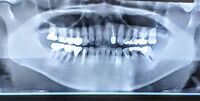

鎌取駅周辺でインプラントをお考えの方へ!フッ素ケアで健康な歯を守る方法 #鎌取駅インプラントフッ素 #鎌取駅 #インプラント #フッ素

土気駅周辺でインプラントを検討中の方へ!フッ素の正しい知識と安全な使用ガイド #土気駅インプラントフッ素 #土気駅 #インプラント #フッ素

誉田駅周辺でインプラントを検討中の方必見!フッ素の正しい活用法と注意点を解説 #誉田駅インプラントフッ素 #誉田駅 #インプラント #フッ素

千城台北駅周辺でインプラントを検討している方へ!フッ素ケアを解説 #千城台北駅インプラントフッ素 #千城台北駅 #インプラント #フッ素

動物公園駅周辺でインプラントを検討中の方必見!フッ素と治療について #動物公園駅インプラントフッ素 #動物公園駅 #インプラント #フッ素